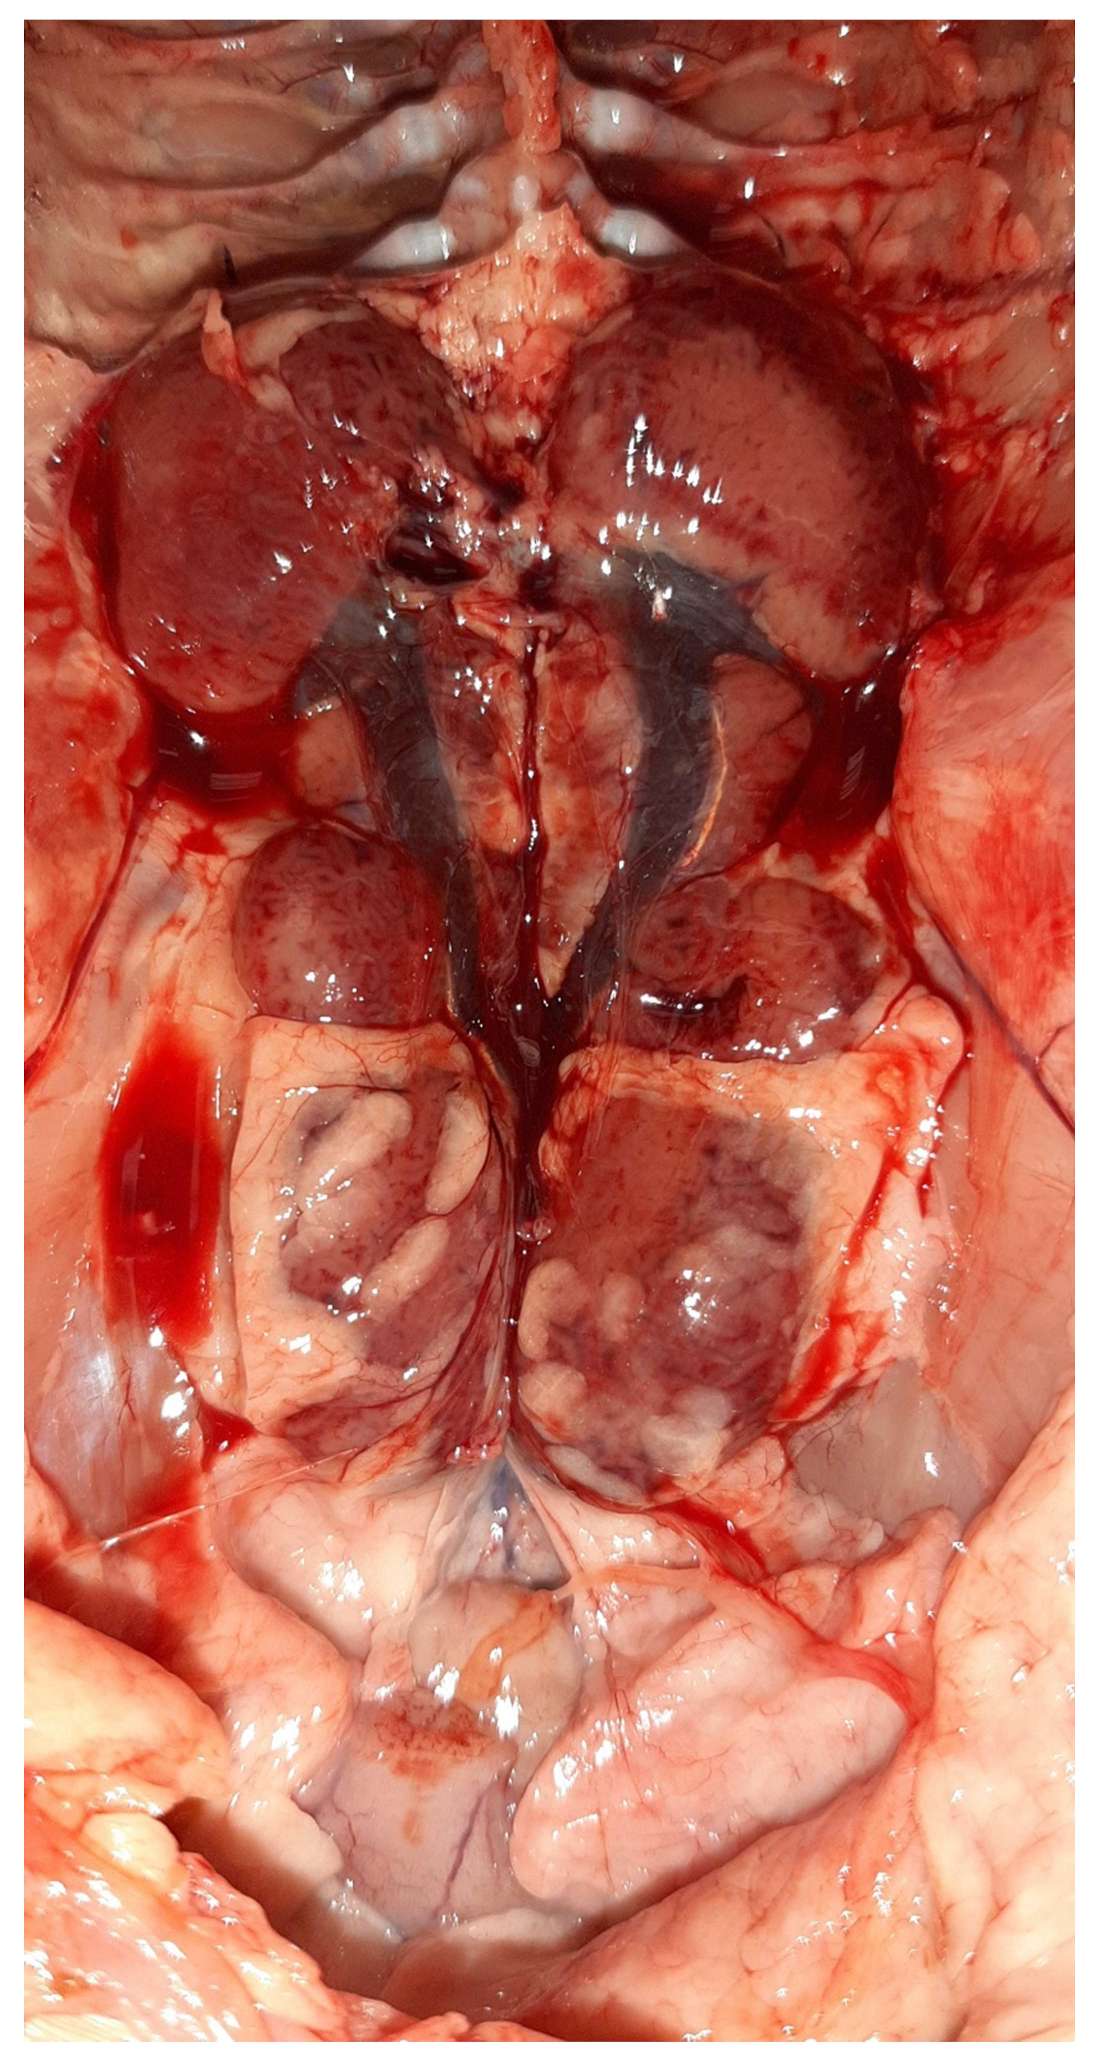

Figure 4.

Gross-pathology findings on a 23-day-old broiler chicken, which was submitted for postmortem examination in the Unit of Avian Medicine, Thessaloniki, Greece during the IBH outbreak. The presence of hemorrhages on the skeletal muscles of the bird is visible, whereas, the liver dominates in the visceral capacity with the lobes of the organ appearing swollen with a marble-like pattern ranging from pale and yellowish to red-dark.

Figure 5.

Post-mortem examination of a 23-day-old broiler chicken from the Flock A. The liver dominates in the visceral capacity with the lobes of the organ appearing swollen with a marble-like pattern ranging from pale and yellowish to red-dark.

On necropsy, most of the chickens had yellowish mucoid diarrhea soiling the feather of the cloaca (Figure 3). Icteric skin and subcutaneous fat were notable in affected birds, while petechial hemorrhages on leg and breast muscles were rarely recorded (Figure 3). During evisceration, the liver dominated the visceral capacity with the lobes of the organ appearing swollen with a marble-like pattern ranging from pale and yellowish to red-dark (Figure 4 and Figure 5). Similarly, kidneys were pale, oedematous, and mottled, enlarged with urates accumulation in the ureters (Figure 6). In many birds, the pancreas was also affected and was slightly inflamed with necrotic foci spotting the surface of the organ (Figure 7). Finally, some birds presented a moderately atrophic Bursa of Fabricius and thymus.